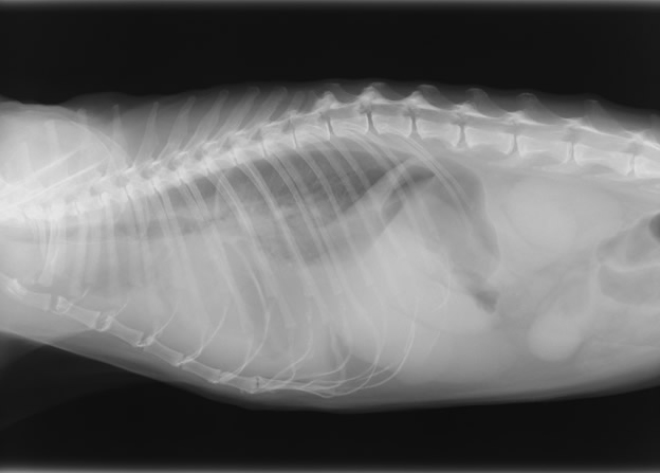

胸部レントゲン検査

X線により心拡大の有無、気管や肺の異常・病変の有無、肝臓うっ血の有無など、内臓の外観の評価を行います。2~3方向から撮影することによって多角的に異常を検出します。

心臓疾患による外観の異常は、たとえば咳の症状が見られた場合には肺や気管にも変化が見られるなど、心臓以外にも現れることがあります。胸部レントゲン検査はスクリーニング検査としても、診断の確度を上げる意味でも重要です。また、犬猫の心臓疾患は肺水腫や胸水を二次的に引き起こすことが多いため、その確認をする上でも有用となります。

HCMによる胸水

HCMによる肺水腫